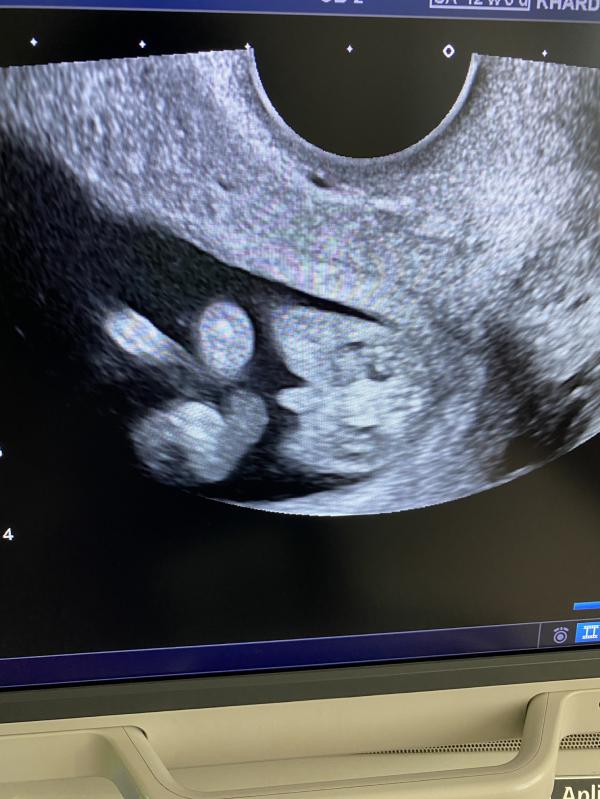

На фото сидит на попе , между ног или Причендал или клитор как сказали 😁

@dmitrysachnov, ну мы на попе сидели 😁 вроде видно все , но кто знает 😁

А вот когда узист начала строить предположения и показывать на экране , меня уже заинтересовало 😁